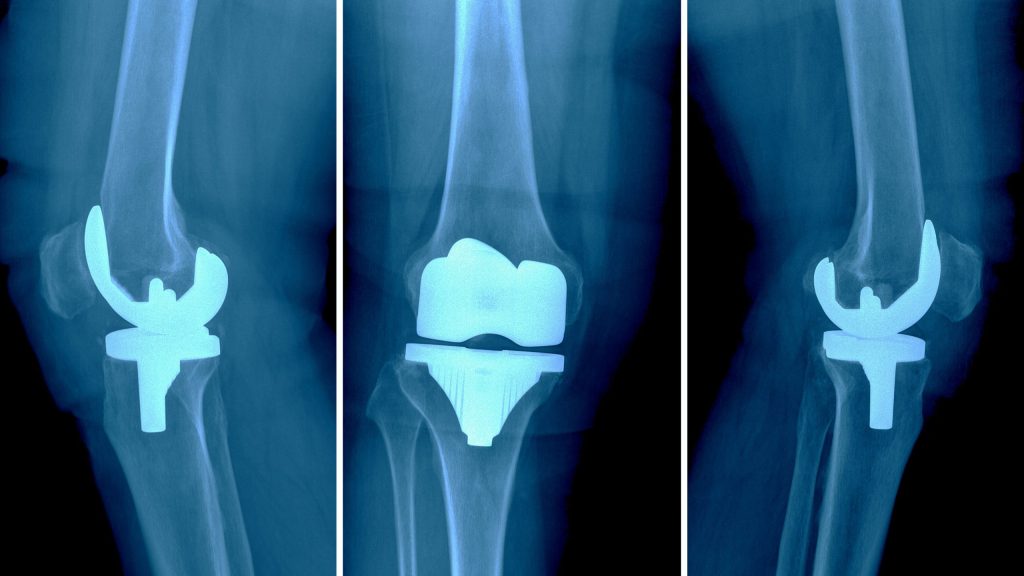

Knee replacement surgery additionally referred to as knee surgery (Arthroplasty) — will facilitate relieve pain and restore operate in severely unhealthy knee joints. The procedure involves cutting away broken bone and gristle from your femoris, shin and kneecap and exchange it with a man-made joint (prosthesis) fabricated from metal alloys, top-grade plastics and polymers.

In determinative whether or not a knee replacement is true for you, associate degree orthopedical doc assesses your knee’s vary of motion, stability and strength. X-rays facilitate verify the extent of harm.